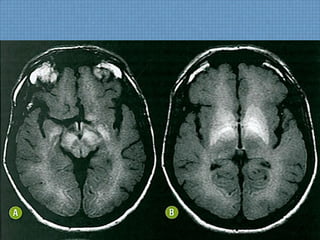

CASO DO SERVIÇO...

ACHADOS DE IMAGEM

• TC:

– Focos hipoatenuantes subcorticais com alguma

extensão ao córtex adjacente parietocciptal;

– Pode haver contraste puntiforme ao meio de

contraste;

– Podem coexistir hemorragias petequiais na transição

SB-SC;